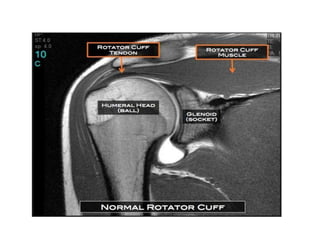

• Most mobile joint in the body

• The cuff envelops and blends with the

glenohumeral capsule on all sides except at

the redundant inferior pouch.

• The tendon of the long head of the biceps-

“fifth tendon” of the cuff-intraarticular but

extrasynovial structure-passes deep in the

“rotator interval”